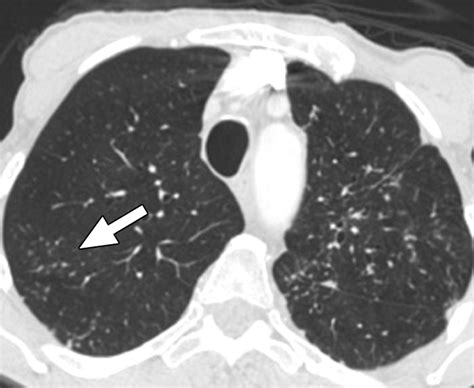

A Node In Lung Ct Scan is defined as a growth or spot measuring less than 3 centimeters in diameter. If the spot is larger than 3 centimeters, it is typically referred to as a lung mass. These structures are relatively common, often appearing as incidental findings on CT scans performed for unrelated reasons, such as a checkup after a minor injury or during a cardiac evaluation. Because these nodules are small, they are frequently invisible on standard chest X-rays, making high-resolution CT scans the gold standard for detection and monitoring.

Most nodules are the result of past exposure to environmental factors or previous infections that have healed, leaving behind a small patch of scar tissue. Other common causes include granulomas—small areas of inflammation often caused by fungal infections—or benign tumors. Because the lung acts as a filter for the body, it is a frequent site for these harmless deposits to accumulate over time.

Characteristics Analyzed by Radiologists

When a radiologist reviews a Node In Lung Ct Scan, they look for specific physical characteristics to determine the likelihood of the nodule being benign or requiring further investigation. By evaluating the size, shape, and internal density of the spot, doctors can categorize the risk level. The following table illustrates how different features are generally interpreted during a clinical assessment: